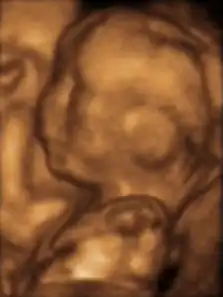

-

Трёхмерное УЗИ 12-недельного плода